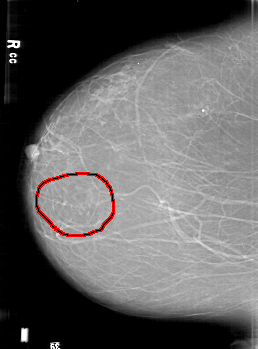

D_4190_1.RIGHT_CC

FILE: D_4190_1.RIGHT_CC.OVERLAY

TOTAL_ABNORMALITIES 1

ABNORMALITY 1

LESION_TYPE CALCIFICATION TYPE FINE_LINEAR_BRANCHING DISTRIBUTION CLUSTERED

ASSESSMENT 0

SUBTLETY 4

PATHOLOGY MALIGNANT

TOTAL_OUTLINES 1

BOUNDARY